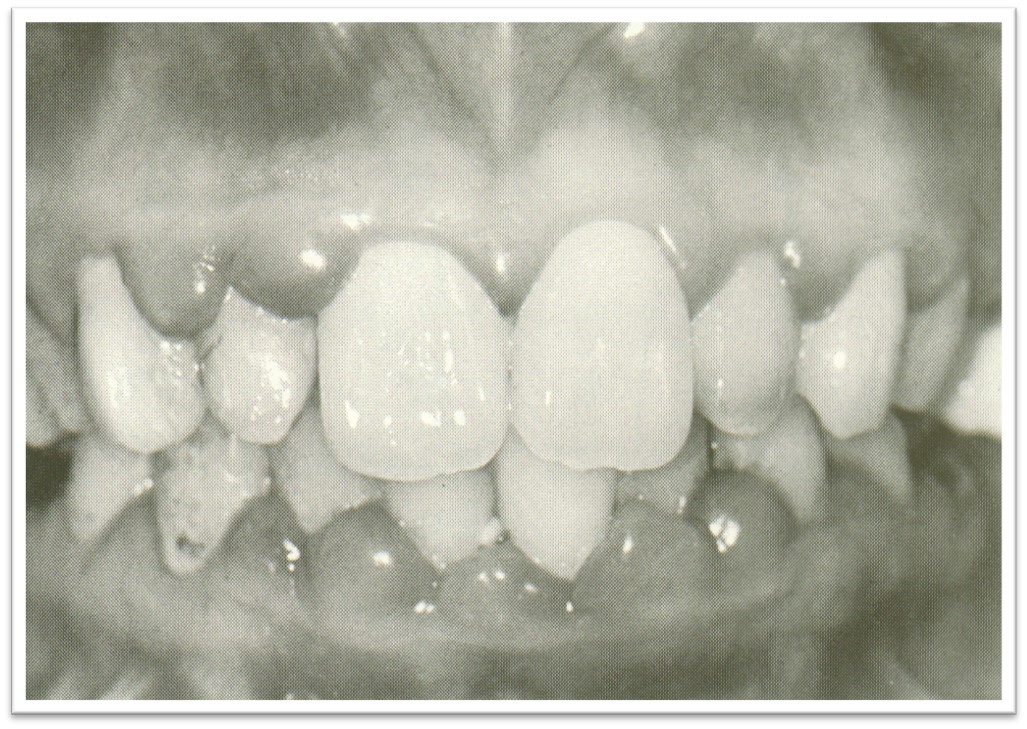

牙龈呈弥漫性增生(图10.1-7)。

图10.1-7 遗传性牙龈纤维瘤病